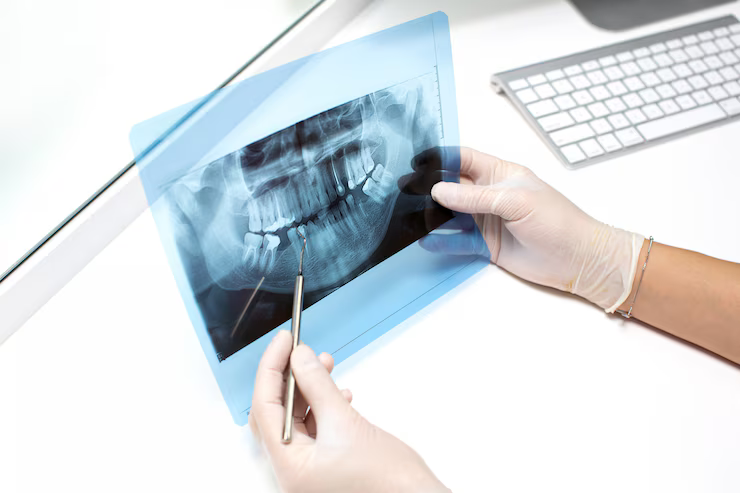

¿Necesitas un diagnóstico detallado para tu tratamiento dental? En MS Dental, tu clínica de referencia en Badajoz, contamos con equipos de radiología dental de última generación para ofrecerte imágenes de alta precisión y garantizar un diagnóstico seguro y eficaz.

Nuestros estudios radiológicos son rápidos, indoloros y mínimamente invasivos, permitiendo detectar patologías, planificar implantes o evaluar estructuras óseas con total fiabilidad. Si buscas una evaluación precisa de tu salud bucodental, estamos preparados para ayudarte.

En MS Dental, utilizamos equipos de vanguardia para garantizar diagnósticos exactos y tratamientos personalizados:

- Radiografías digitales – Menor radiación y resultados inmediatos.

- Tomografía Cone Beam 3D – Imágenes tridimensionales para cirugías e implantes.

- Telerradiografía lateral y frontal – Esencial para ortodoncia y estudios craneofaciales.

Nuestro equipo de radiólogos y odontólogos especializados analiza cada caso en detalle, asegurando la mejor planificación para tu tratamiento.

Entendemos que un diagnóstico rápido y preciso es clave para tu tratamiento dental. Nuestros equipos de radiología digital en Badajoz ofrecen imágenes de alta calidad en segundos, permitiendo a nuestros especialistas evaluar tu caso al instante. ¿Necesitas una radiografía periapical, una ortopantomografía o un TAC 3D? Con nosotros, obtendrás resultados confiables sin esperas.